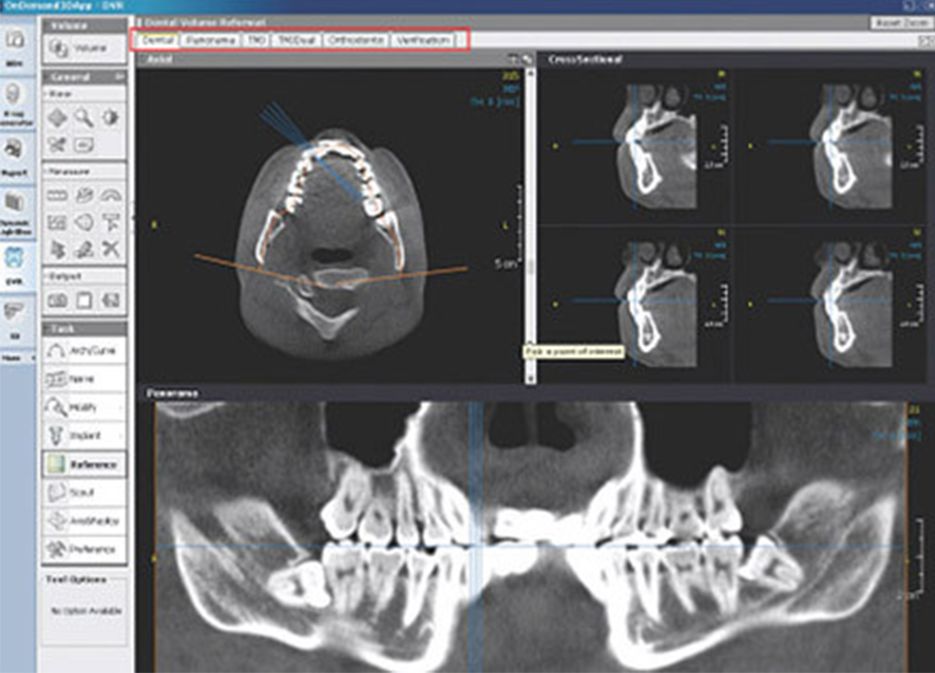

OnDemand3D™ – solutie completa de imagistica utilizata de medici stomatologi, ortodonti si nu numai. OnDemand3D™ este un software puternic pentru afisarea, evaluarea, prezentarea si documentarea datelor de volum 3D ale unui dispozitiv CBCT. OnDemand3D™ permite stocarea datelor DICOM si include diverse instrumente personalizabile pentru diagnosticare si planificarea tratamentului. Software-ul bazat pe module, este flexibil si usor de extins, si in acelasi timp permite accesul din orice locatie.

OnDemand3D™ Dental include functii de tratament dentar si planificare a implantului, cum ar fi aspectul MPR, plasarea implantului, verificarea si analiza TMJ. Permite comunicarea PACS.

Modulul Dental prezinta o mare parte din functiile modulului DVR. Spre deosebire de modulul DVR, modulul Dental ofera si functii ale modulului 3D, precum zoom-ul 3D care permite marirea detaliilor 3D.

Functionalitati: planificare implanturi, analiza TMJ, zoom 3D, trasare nerv.